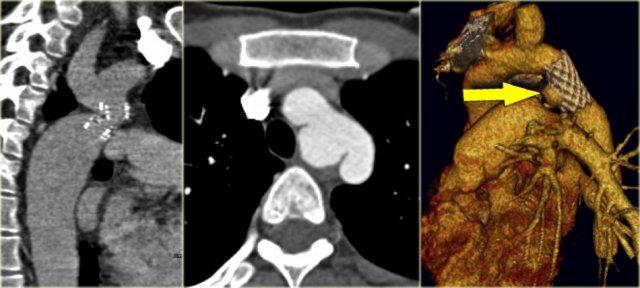

On the left a patient with a right arch with an aberrant left subclavian (indicated by the yellow arrow).

There is a right arch and the left subclavian artery is the last branch of the aortic arch, indicating that this is an aberrant left subclavian.

Medially to the left subclavian artery we see the left common carotid, that originates from the right side and has an oblique course to the left.

The yellow arrow indicates the azygos vein.

The green arrow indicates the left superior intercostal vein, a normal variant, that we will discuss later.

Same patient.

Posterior oblique view of volume rendered image to show the aberrant left subclavian artery.